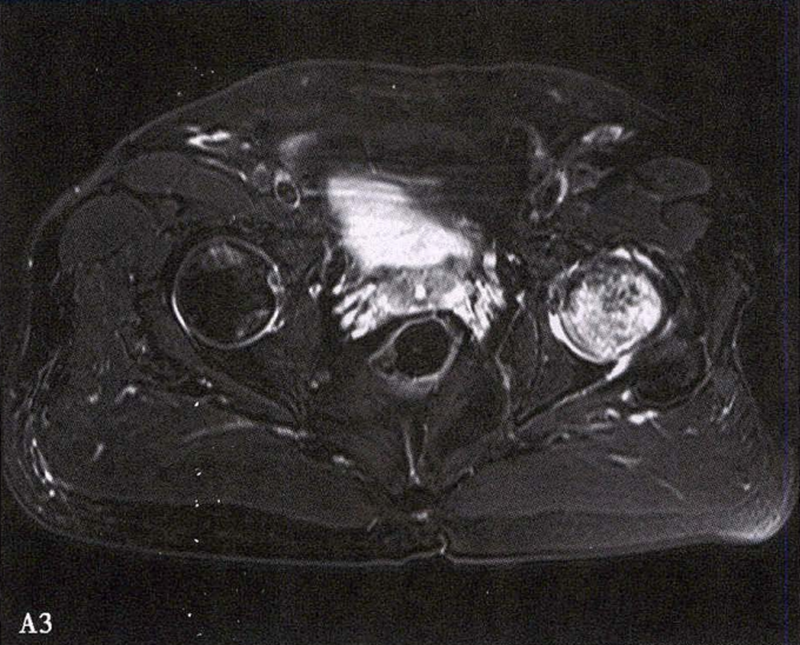

A.男性,71岁,双侧股骨头坏死,右侧Ⅰ期、左侧Ⅲ期。X线片示双侧股骨头形态可,右股骨头未见明显密度改变,左股骨头关节面下见局限性骨密度减低及增高区(A1)。MRI(T2加权像)示右股骨头内双线征,左侧不规则形混杂信号,坏死区远端骨髓水肿(A2、A3)。